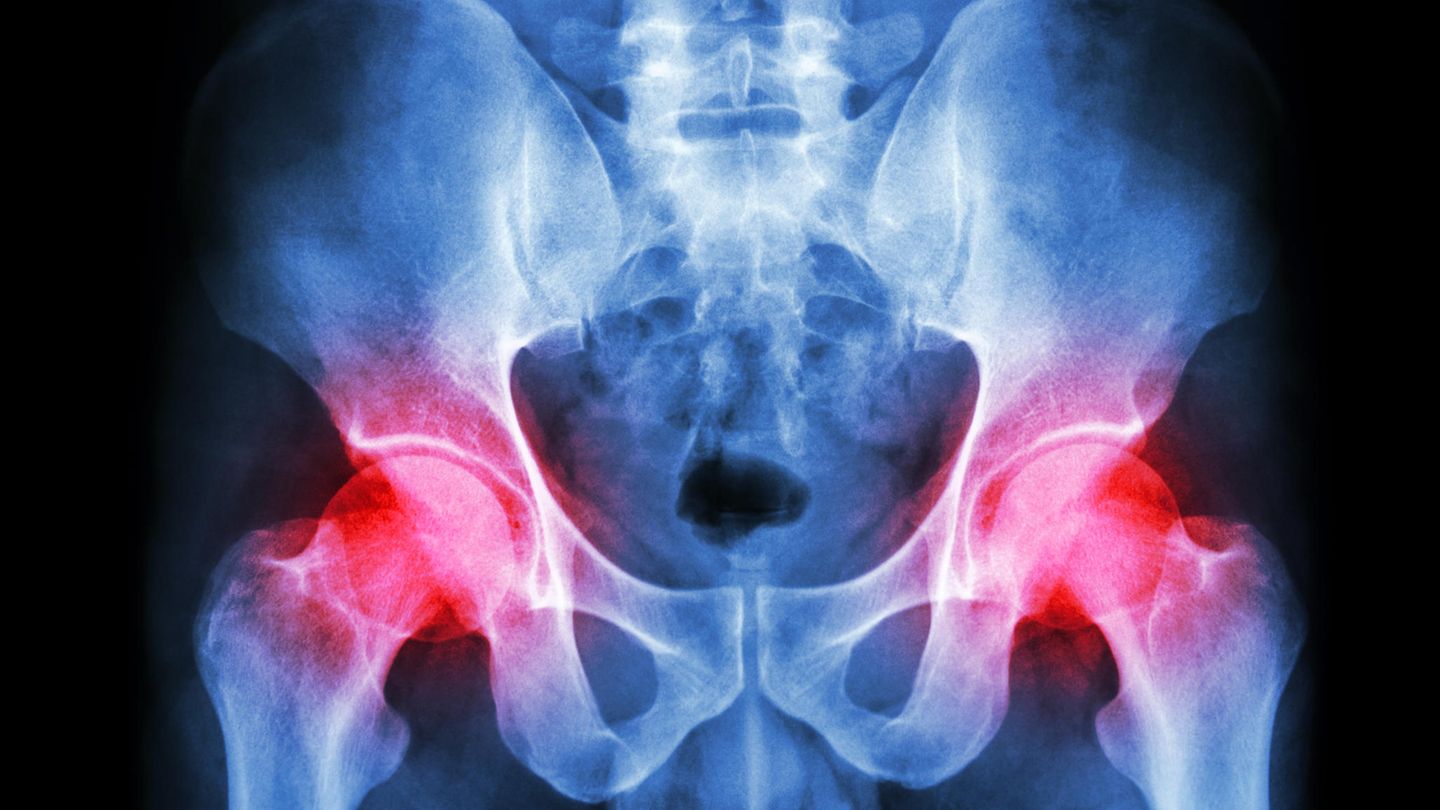

Immer neue künstliche Hüftgelenke - doch die Schmerzen bleiben. Was steckt dahinter?

Ein Mann hat seit Jahren Hüftschmerzen – trotz immer neuer Kunstgelenke. Mithilfe der Metallwerte im Blut löst ein Orthopäde das Rätsel.